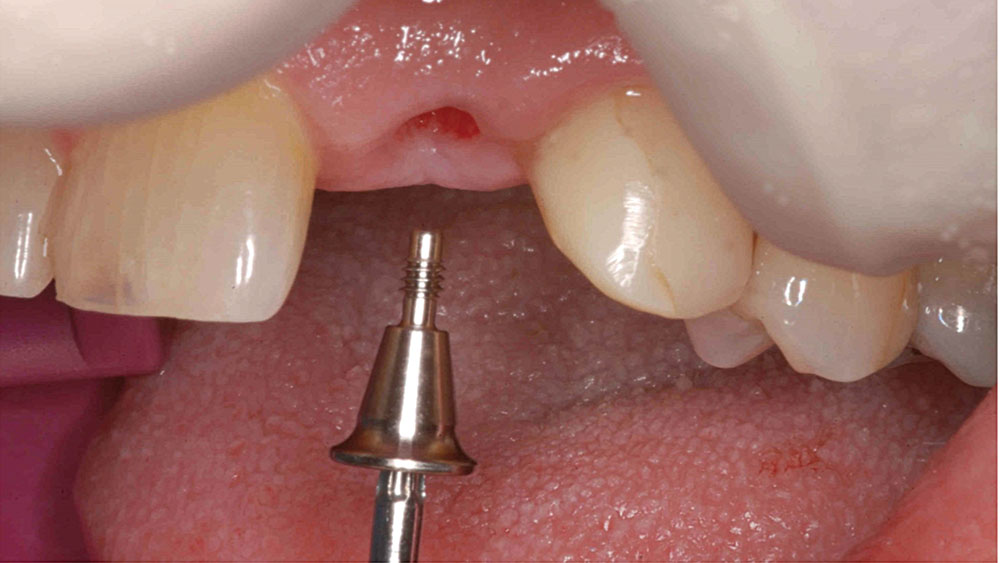

To achieve an optimal functional and esthetic outcome, the implant must be placed correctly with regard to trajectory, adjacent vital anatomy, and buccolingual, apicocoronal and mesial-distal positioning. Situating the implant so that the edges of the osteotomy are at least 2 mm from the buccal and lingual cortical plates, 2 mm from adjacent roots, 2 mm from vital structures, and 2–3 mm below the crest of tissue will keep the implant within the envelope of acceptability. The implant trajectory should emerge lingual to the incisal edge of the planned restoration, which allows for a screw-retained crown.

This case is an example of an ideal clinical situation for dentists who are new to placing implants in the esthetic zone. The patient requested treatment for a fractured upper lateral incisor. After extraction, grafting and healing, ample bone and soft tissue were present, and an implant was placed in optimal position for an esthetic result. The screw-retained restoration predictably restored form and function, illustrating the beautiful results that can be achieved by observing simple surgical and prosthetic guidelines.